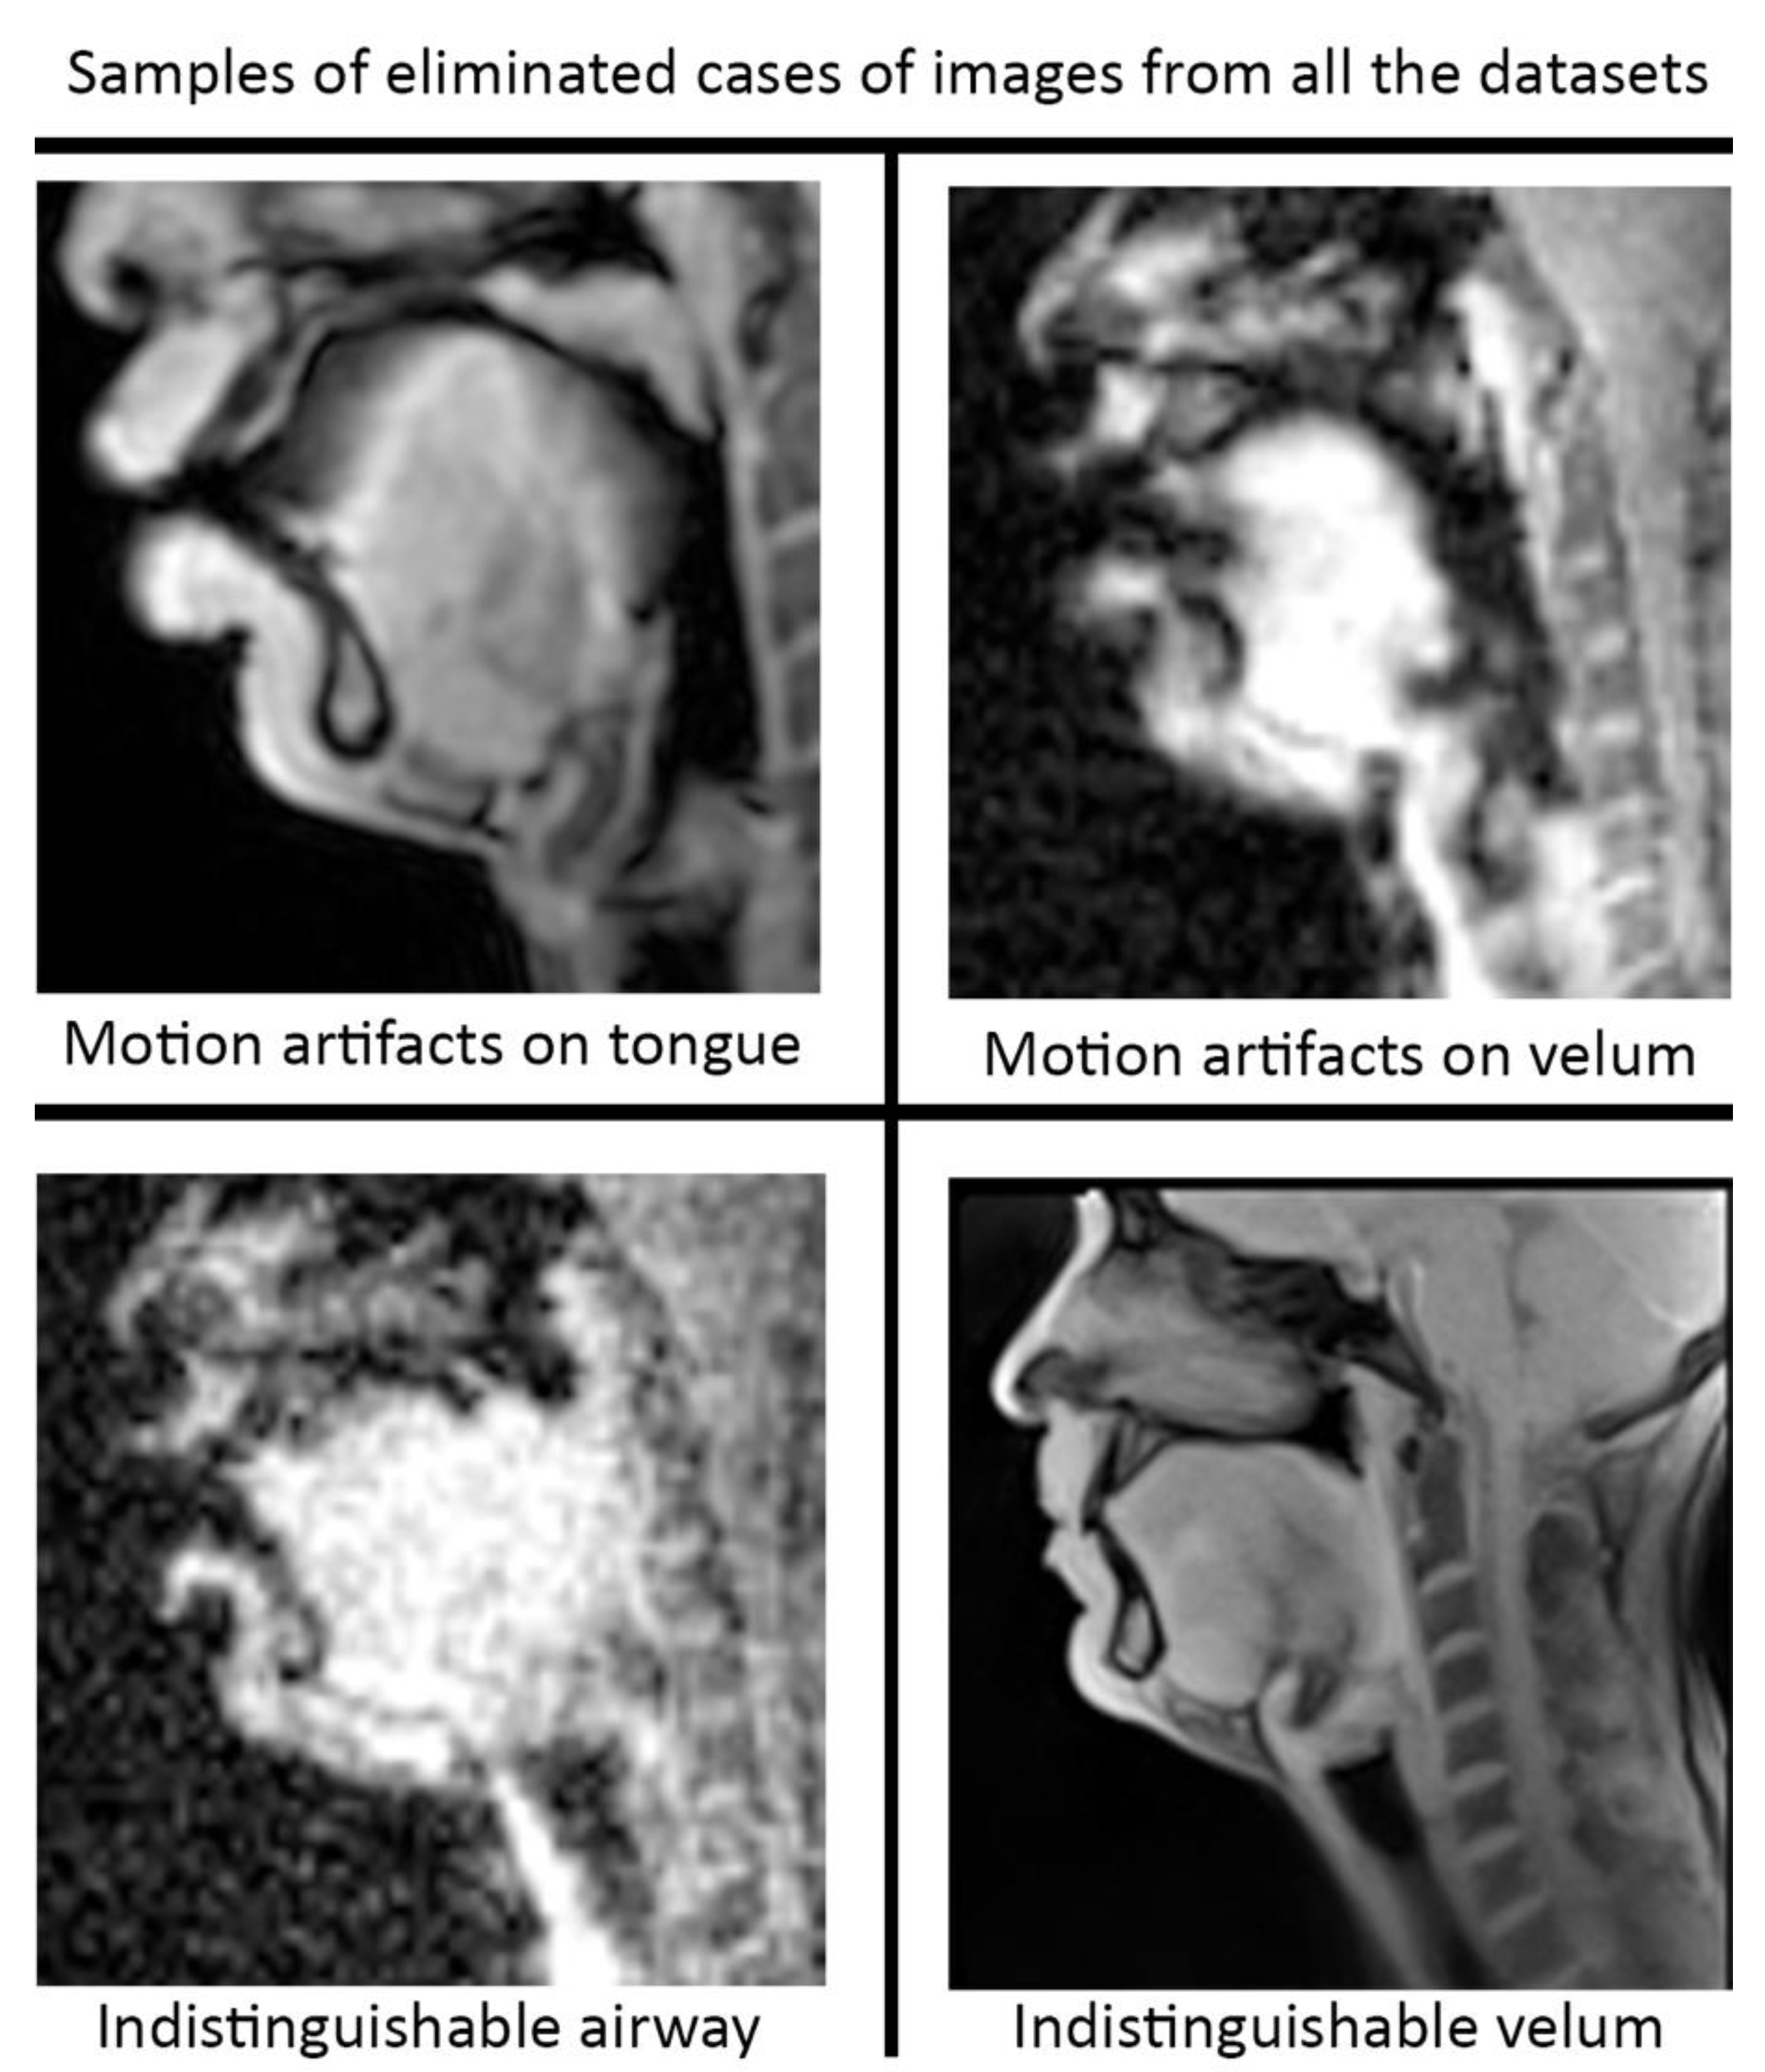

Pre-processing and post-processing: In this study, we applied pre- and post-processing to improve the STL U-NET performance. First, data curation from the different speech MRI protocols was applied while re-training the STL U-NET model. Each protocol may contain images where the airway, tongue boundary, or velum boundary are poorly visualized due to swallowing, or images with motion artifacts and un-resolved alias artifacts. Figure 4 shows examples that were omitted from the training set. The input dynamic images from the protocols were cropped in pre-processing to focus on the regions of interest in the vocal tract and surrounding soft tissue vocal organs. Images were then re-scaled to a 256 × 256 image matrix size. Since the reconstructed images may contain non-uniform intensities, we applied a bias field intensity correction algorithm to provide uniform intensity across the field of view. In our earlier experiments [26], we found that a soft intensity thresholding on the images can improve the segmentation accuracy of U-NET segmentation. Next, we performed soft-intensity thresholding to remove pixels with image intensities less than 20 on a 255-intensity scale. Output segmentations may occasionally contain segmentation boundaries with blurred or fog-like regions that cannot be corrected by modifying the network. Since the majority of the segmented pixels fall in the 200–255 intensity range, and the blurred and fog-like regions have segmentation intensities in the range of 0–70, we applied a thresholding up to 70 to remove the blurred regions. Following thresholding, we binarized the segmentations to have all other bright pixels attain 255-pixel intensity. Once binarized, breaks in the inside morphology of each of these articulators may occur. To avoid such gaps, we have used dilation with a line structuring element of size 5 pixels to fill those gaps. Further, small independent regions on the segmentation map that are not relevant to the morphology of the vocal structures may occur (e.g., on the nasal airway, on the spine). Since segmentations of the individual vocal structures have a minimum number of pixels, we removed all independent segmentation maps with a total connected pixel count of less than 100 pixels. All pre-processing and post-processing functionalities were created using MATLAB R2021 (Mathworks, Natick, MA, USA).

Figure 4. Data curation was applied prior to re-training the STL U-NET model. Image frames where the airway, tongue, or velum boundaries were blurred or indistinguishable. Shown here are examples of omitted frames from all the protocols.